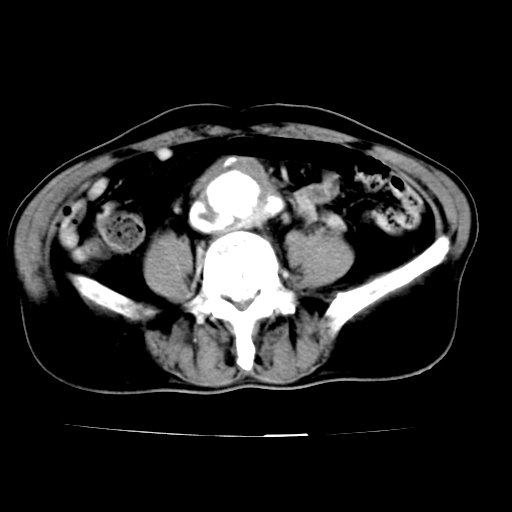

标题: V0243:右髂总动脉瘤附壁血栓形成?破裂?动静脉瘘? [打印本页]

标题: V0243:右髂总动脉瘤附壁血栓形成?破裂?动静脉瘘?

男,75岁,腹痛月余,彩超发现脐周腹主动脉异常回声。临床诊断:腹主动脉瘤。

ct诊断:右骼总动脉囊性动脉瘤并瘤内附壁血栓形成,与下腔静脉之间形成动静脉瘘。

请问各位老师:能排除动脉瘤破裂的可能吗?

各位老师注意到下腔静脉的充盈缺损了吗?注意到动静脉漏了吗?

当时是扫描的标准动脉期,可是下腔静脉与腹主动脉同步强化且幅度一致。所以我想动静脉瘘是存在的。